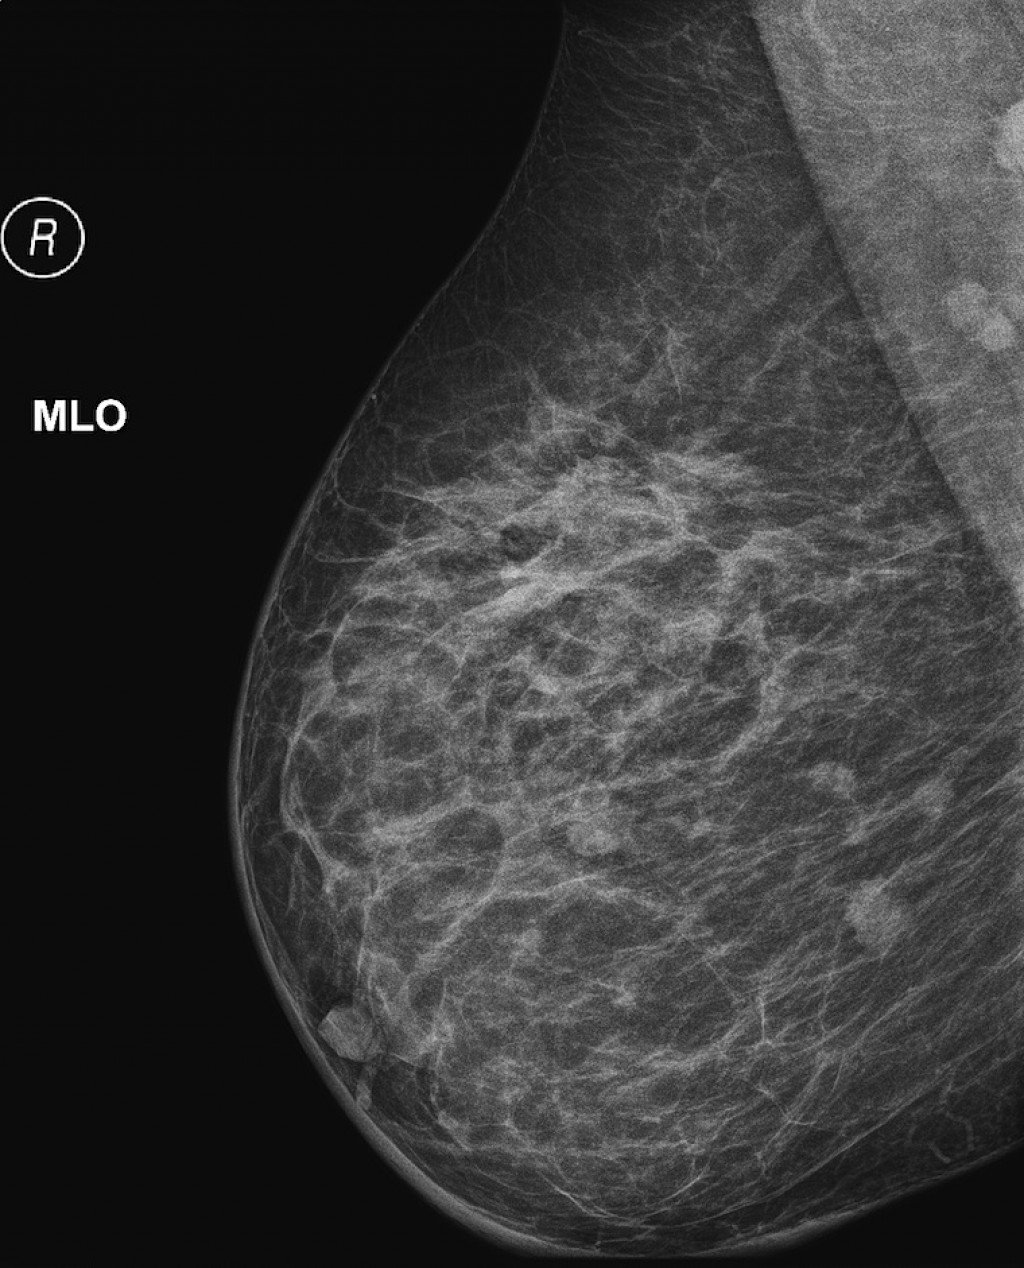

Фиброаденома молочной железы - доброкачественное образование, которое часто встречается у женщин. Оно может быть обнаружено при помощи различных методов диагностики, включая маммографию. Ниже представлены фотографии, помогающие понять, как выглядит данное заболевание.

Маммография и ее роль в диагностике фиброаденомы молочной железы

Маммография - это рентгенологическое исследование молочных желез. Оно позволяет выявить различные изменения в тканях, включая фиброаденому. На маммограммах можно увидеть структурные особенности опухоли и отследить ее динамику во времени.